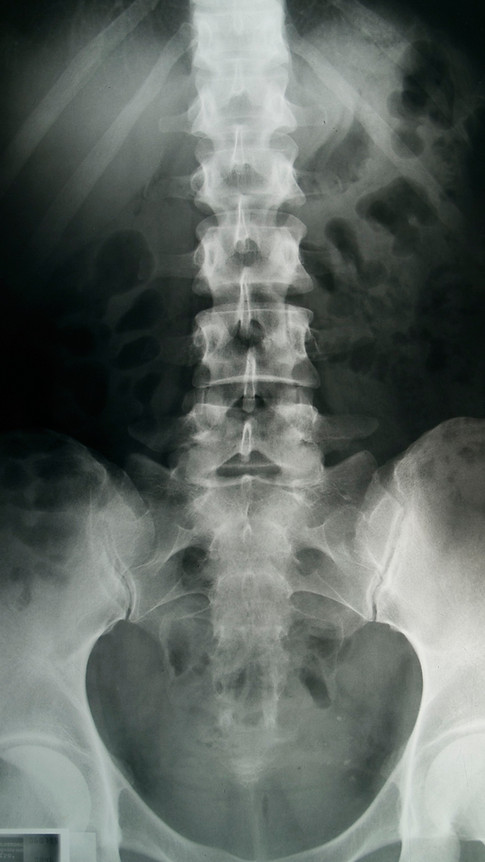

Suffering From Lower Back Pain?

Lower back pain is one of the most common issues we see- whether it's caused by work , sport, posture or everyday life.

If you're experiencing stiffness, aches, sharp pain, or recurring flare ups, it's time to address the root cause.

Common Causes Of Lower Back Pain

Lower back pain can come from a range os issues, including:

poor posture or desk work

Muscle strain or imbalance

Joint dysfunction

Disc problems

Sports injuries or overuse